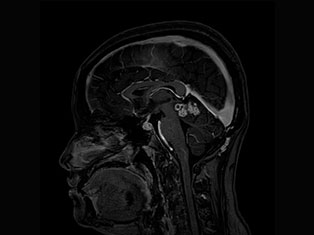

Brain Tumors

A brain tumor is a mass or growth of abnormal cells in your brain. Many different types of brain tumors exist. Some brain tumors are noncancerous (benign), and some brain tumors are cancerous (malignant).